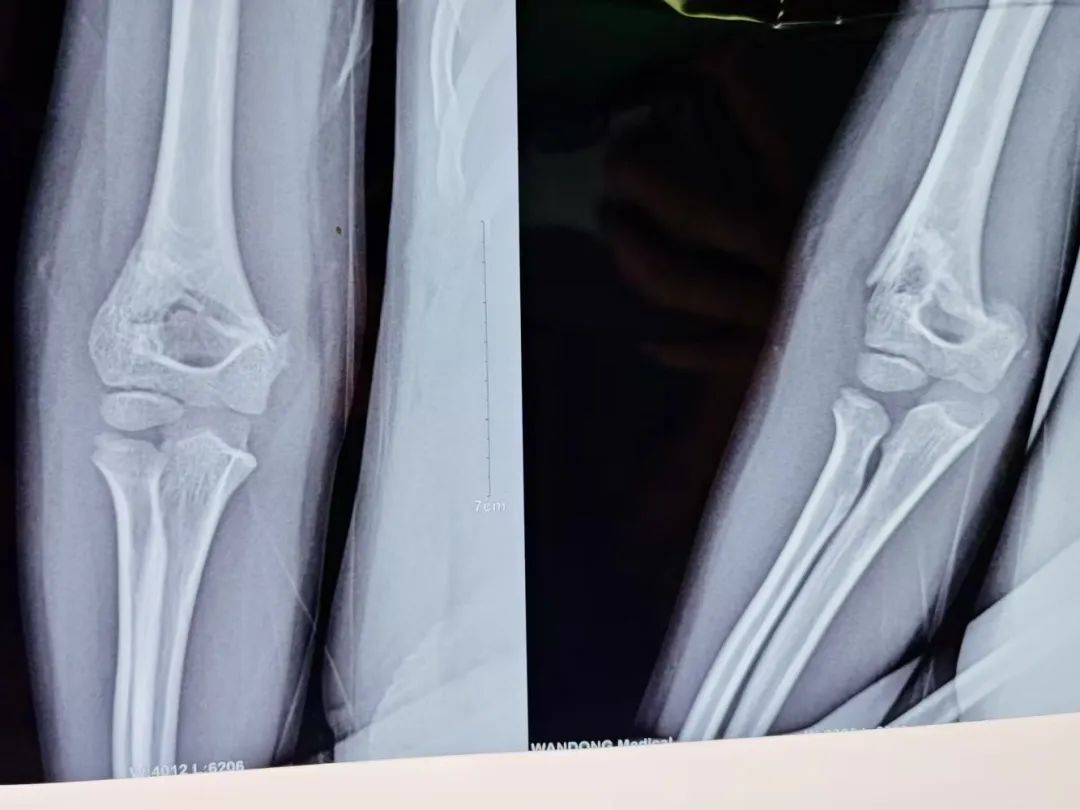

近日,一名年幼患儿在玩耍平衡车时不慎摔倒,导致"肱骨髁上骨折"。由于患儿年龄小、疼痛剧烈,且骨折移位明显、断端极不稳定,随时面临二次伤害风险。危急时刻,家属第一时间将孩子送至周口人合医院就诊。 我院创伤中心立即启动"急诊绿色通道",骨三科医疗团队快速响应,经详细检查评估后,决定为患儿实施"肱骨髁上骨折切开复位内固定术"。手术团队凭借丰富的儿童骨折治疗经验,采用精准的微创技术,成功完成骨折复位固定,最大限度减少了手术创伤。 术后,在医护人员的精心照料下,患儿恢复顺利,骨折愈合良好,现已能进行适当的功能锻炼。家属感激地说:"从急诊到手术再到康复,每个环节都让我们感受到专业与温暖!" 术 前

术 后